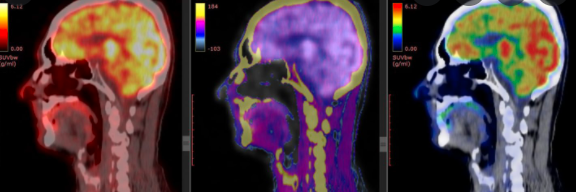

UE 4.10 Explorations et traitements en médecine nucléaire